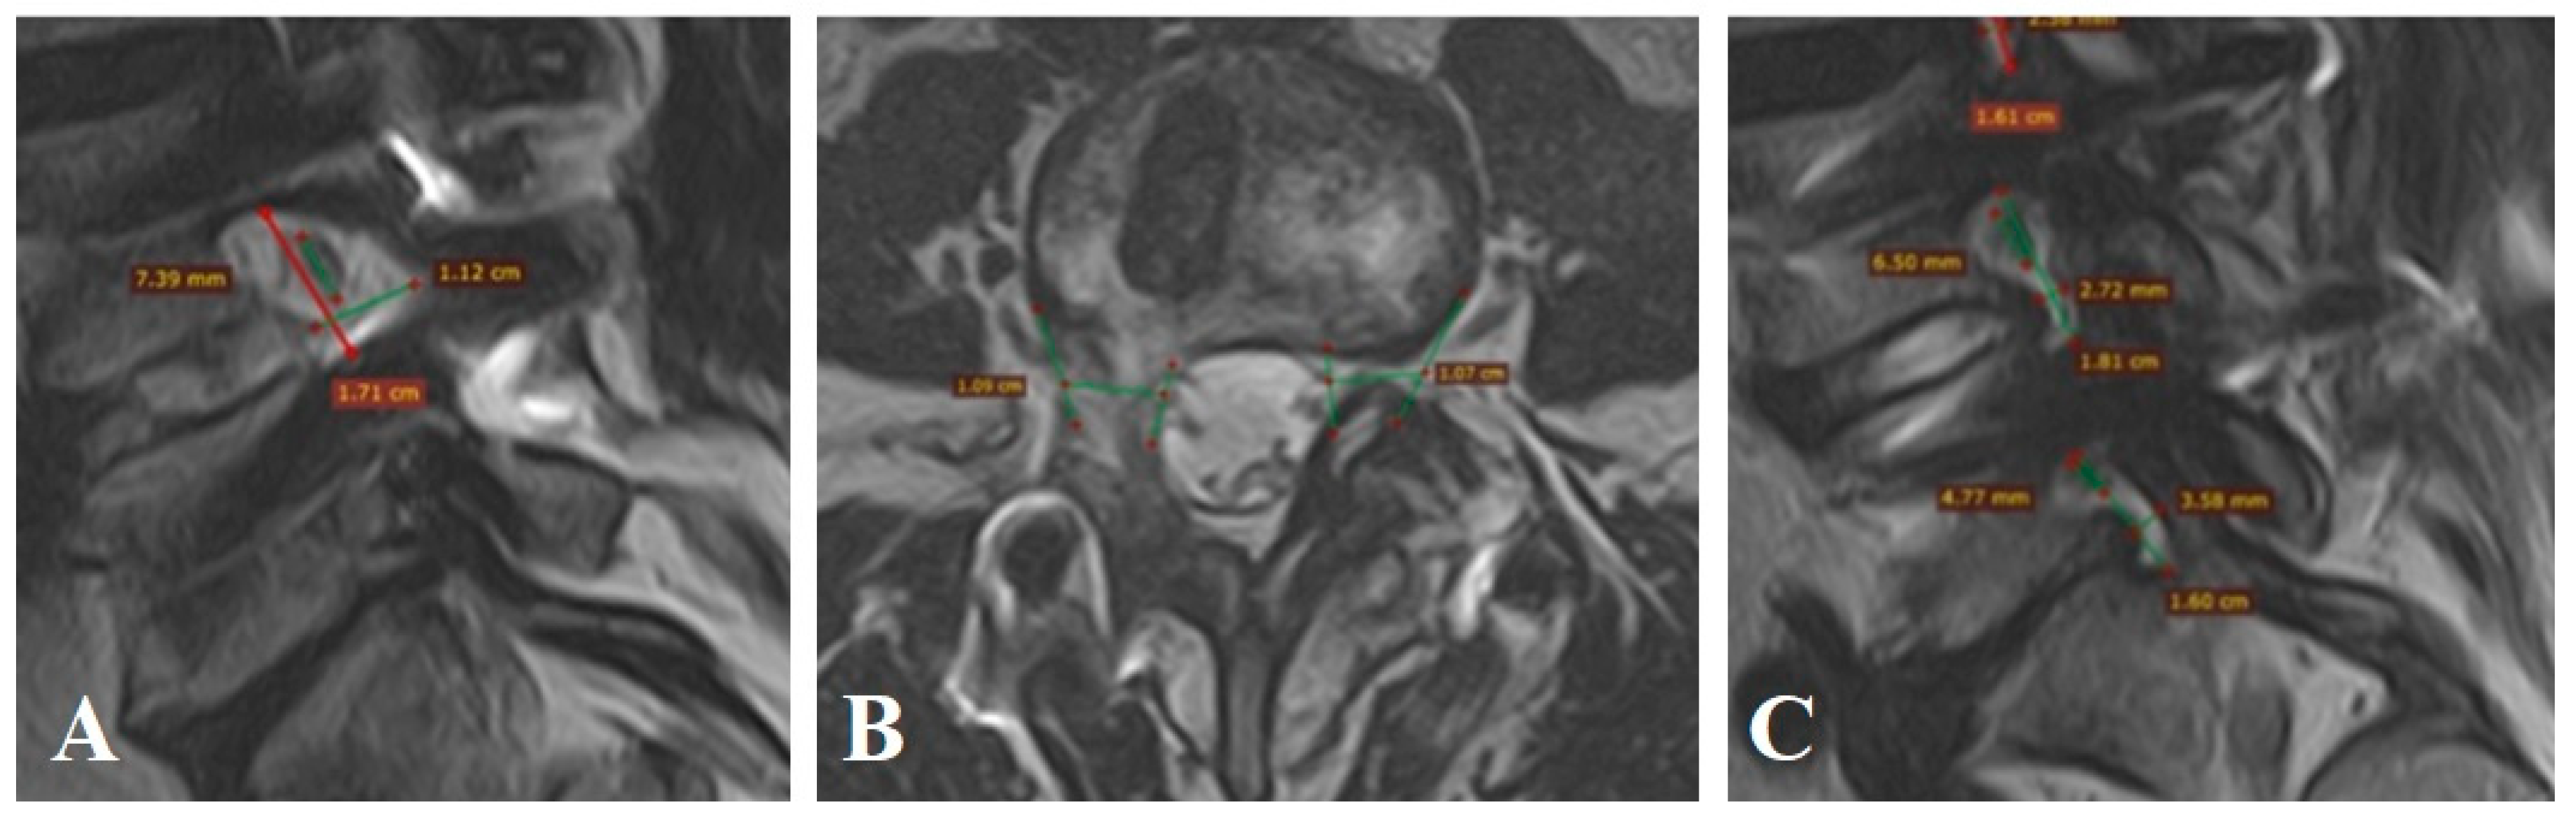

Patient n° 4 is a 64-year-old female, complained of lumbar pain with radiation to the left lower extremity, unresponsive to conservative therapy for over three months. MRI revealed Grade 3 foraminal stenosis at L5–S1. Left FC volume was 323.2 mm3, nerve volume 220.6 mm3, and nerve occupancy was 68.2% (Figure A4A–C). Right FC volume was 694.3 mm3, nerve volume 316 mm3 (occupancy: 34.1%). VAS scores were 8 cm in the leg and 5 cm in the back. Instability was rated at 4 points per White–Panjabi, and ODI was 46.

Microsurgical foraminotomy and decompression of the left L5–S1 root were performed. Postoperative FC volume increased to 768.4 mm3 with unchanged nerve volume (220.6 mm3), reducing nerve occupancy to 28.7% (Figure A4D,E), representing a 57.9% volumetric gain. VAS scores improved to 1 cm (back and leg). ODI improved to 18 at 12 months.

Figure A4.

MRI of patient n° 4.